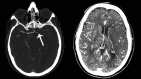

Standard imaging in acute stroke is undertaken with the aim of diagnosing the underlying cause and excluding stroke mimics. In the presence of ischaemic stroke, imaging is also needed to assess patient suitability for treatment with intravenous thrombolysis. Non-contrast CT is predominantly used, but MRI can also exclude any contraindications to thrombolysis treatment. Advanced stroke imaging such as CT and MR angiography and perfusion imaging are increasingly used in an acute setting. In this review, we discuss the evidence for the application of these advanced techniques in the imaging of acute stroke.